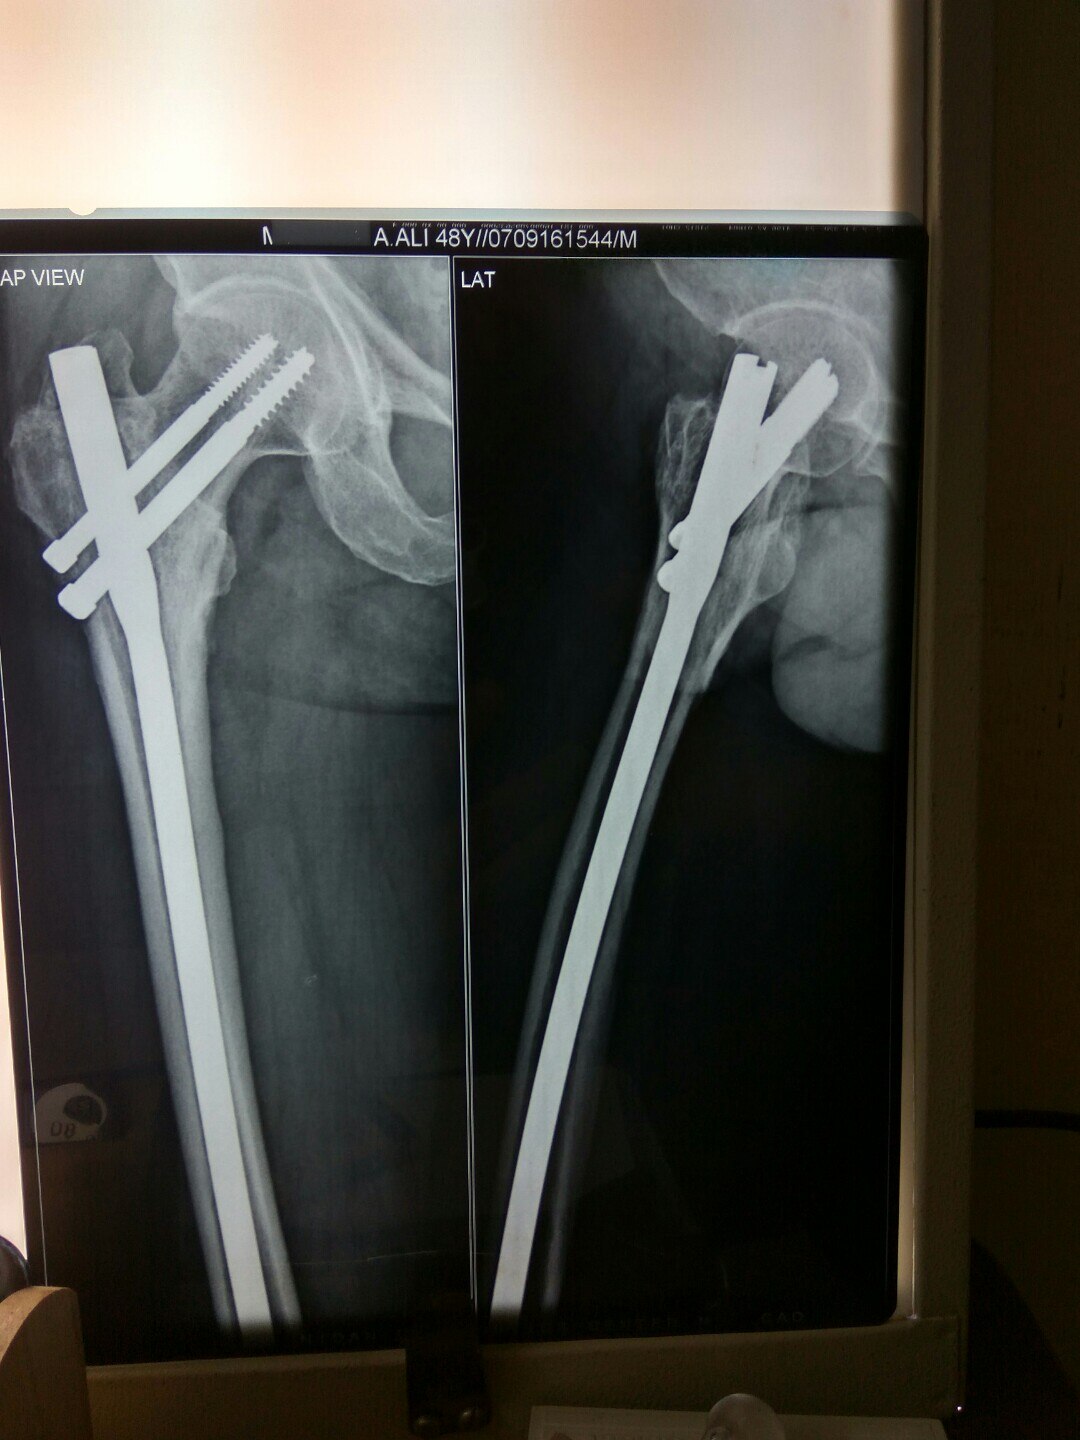

Dr. Sonawane Orthocare clinic is a centrally located Orthopedic Clinic In Pune city near Swargate at Hirabaug Business Centre, Hirabaug chowk, Tilak Road, Shukrawar peth and has easy accessibility from all parts of the city with multiple modes of travelling and enough parking spaces for patients’ own vehicles. Clinic is very modern and stylish and has air conditioned waiting area with comfortable sitting arrangement along with other amenities like TV, Wi-Fi, newspapers. There is hassle-free appointment and consultation system which is totally computerized. Patients get system generated appointment messages, reminders for follow-up dates and prescriptions through messages and emails. So its easy to keep track, keep and carry records and access it anywhere in the world. Clinic offers in-house digital X-ray, pathology tests and physiotherapy facilities at very reasonable rates. This makes the clinic a one stop destination for the patients they don’t need to go anywhere else for these facilities, saving lots of time and effort to get the treatment. We at Dr. Sonawane Orthocare clinic are committed for the best orthopedics care and proud to be one of the best orthopedics clinics in Pune.